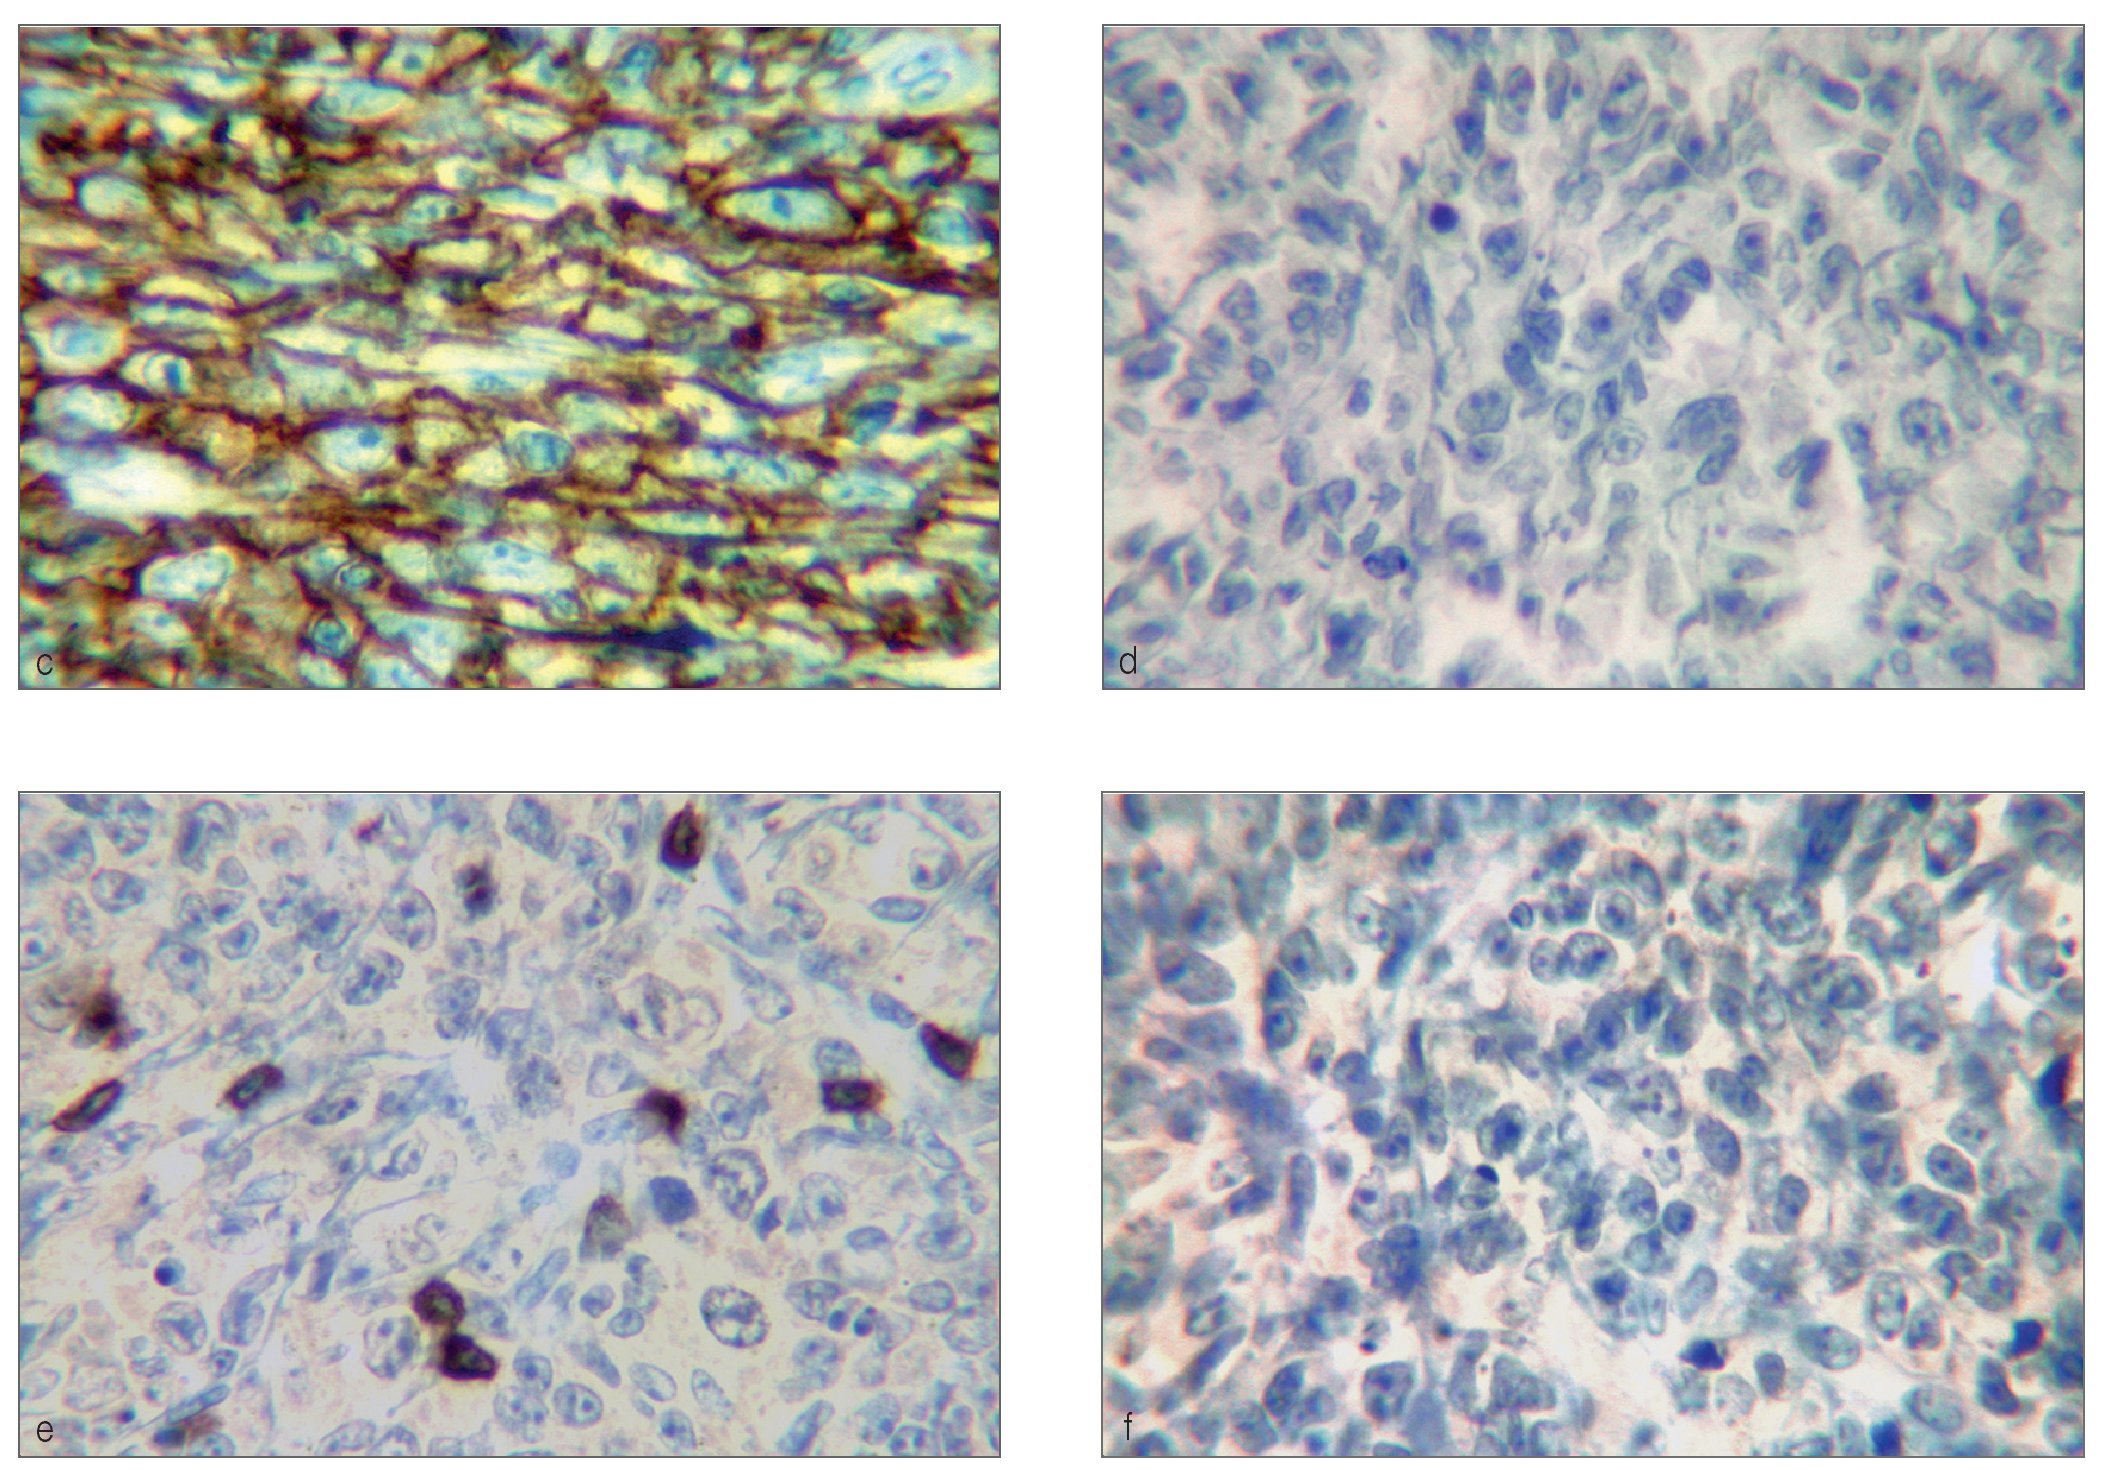

El examen histológico mostró un fuerte infiltrado difuso constituido por células blásticas linfoides grandes que presentaban núcleos ovoides y nucleolos prominentes, con presencia de numerosas mitosis atípicas (figs. 2a y 2b). La inmunohistoquímica mostró células pleomórficas positivas para CD20 y negativas para CD30, CD3, y anticuerpos Alk, confirmando el diagnóstico de LNH difuso de células B grandes (figs. 2c a 2f). Una vez completado el estudio se descartó linfoma sistémico.

Figuras 2c a 2f. Inmunohistoquímica que muestra células pleomórficas difusamente positivas para CD20 (c) y negativas para CD30 (d), CD3 (e) y anticuerpos Alk (f) (inmunoperoxidasa; 40 aumentos originales). En la figura 2e, solo son positivos algunos linfocitos T.